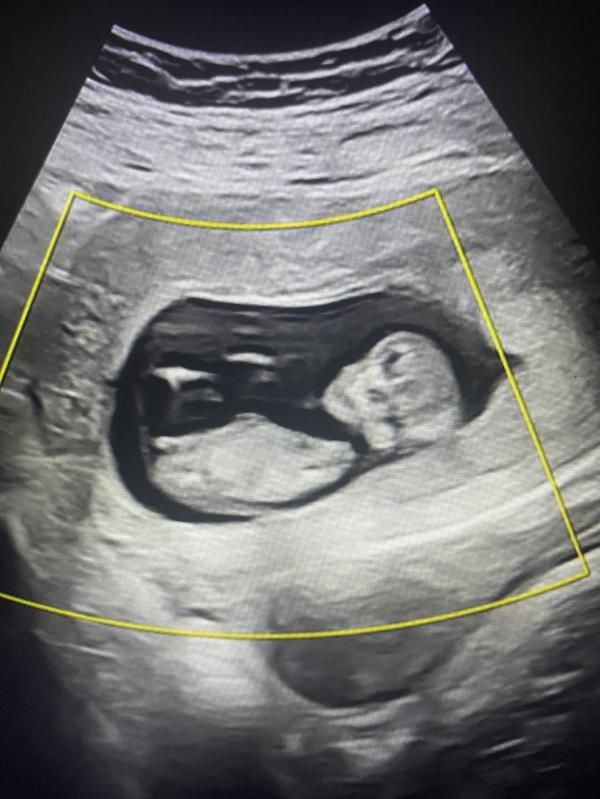

2-ой скрининг.

Слава Богу, всё в порядке.

Запаковали пол ребенка в конверт.

Ровно через сутки узнаем, кто там живёт внутри меня.

Девочки, через неделю скрининг, где узнаем пол малыша. Предлагаю пока погадать, кто у нас) сделала фото с видео, где видно бугорок. Сама я в этом не бум-бум.